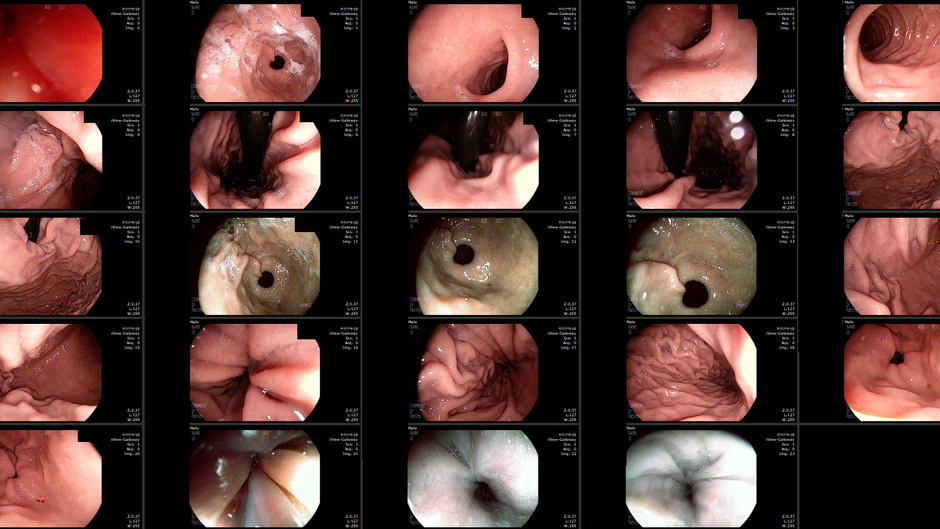

Gastric antral vascular ectasia (GAVE), 위전정부 혈관확장증 소견 - 동대문구 답십리, 용두동, 우리안애 우리안愛 내과

70대 후반 남자 19, 20, 22년 한번씩 진료 혹은 어르신 독감 접종 위해 방문한 분으로 23년 1월부터 기존약 참조하여 혈압/당뇨 처방 22년 말 마지막 혈액평가 검진 및 당뇨 평가위해 내원 내시경에서 아래와 같은 모습; GAVE -...